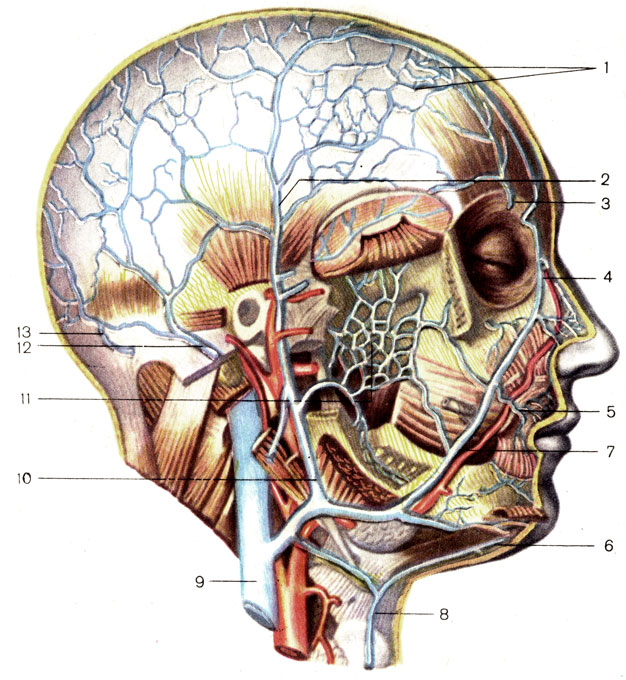

Анатомия внутренней яремной вены: КТ изображения